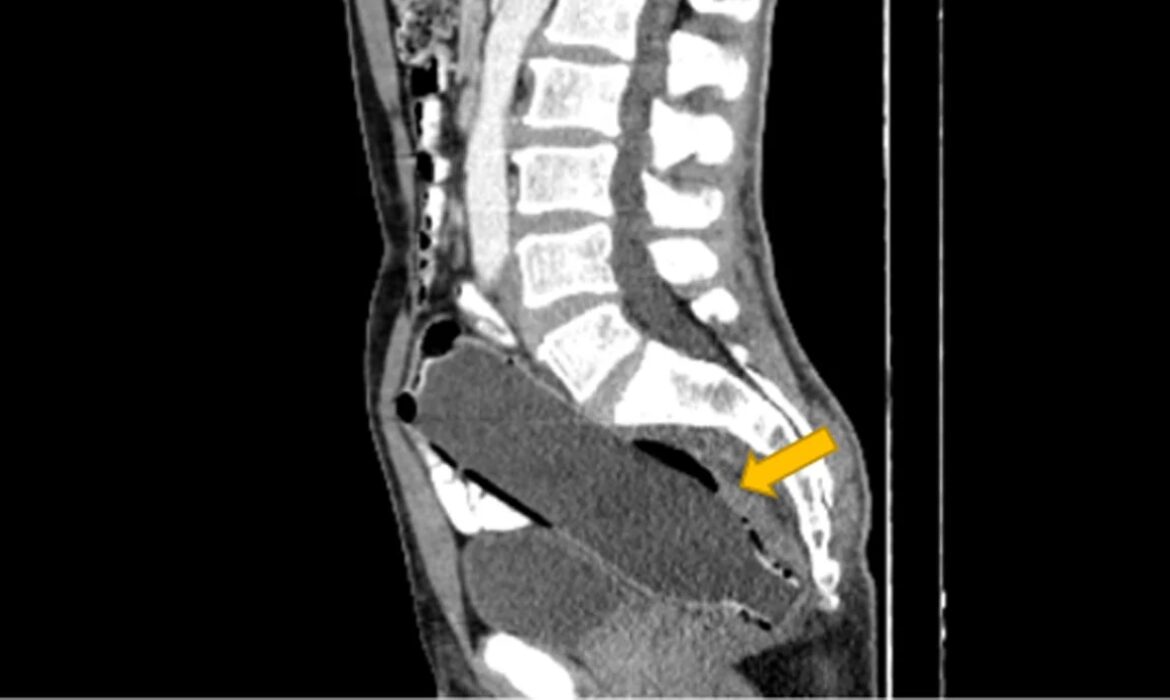

Ο άνδρας συνέχισε να κρύβει με επιτυχία το οδυνηρό μυστικό του, μέχρι που αποκαλύφθηκε στους γιατρούς μέσω αξονικής τομογραφίας.

Σύμφωνα με ένα άρθρο στο Clinical Case Reports Journal, ο άνδρας απέφυγε να αναφέρει ότι είχε τοποθετήσει το αντικείμενο μόνος του, λόγω «αμηχανίας» και «φόβου για τη γυναίκα του».

Η μελέτη αναφέρει ότι είχε εισαγάγει το μπουκάλι με το κάτω μέρος να μπαίνει πρώτο, προκειμένου να χρησιμοποιήσει το επάνω μέρος ως λαβή για να το τραβήξει έξω.

Όταν όμως ήρθε η ώρα να γίνει αυτό, το αντικείμενο παγιδεύτηκε στο παχύ έντερο του άνδρα. Οι γιατροί στο νοσοκομείο Imam Khomeini στο Sari δεν ανέφεραν γιατί ακριβώς το μπουκάλι κόλλησε εκεί, αλλά είπαν ότι η σεξουαλική ικανοποίηση κρύβεται συνήθως πίσω από τέτοιου είδους καταστάσεις. Ο άνδρας ήταν επίσης γνωστό ότι είχε ιστορικό κατάθλιψης, σύμφωνα με το Clinical Case Reports.